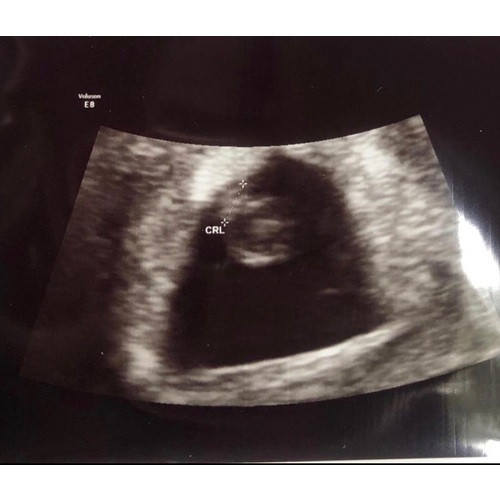

Vandaag een echo gehad en ze schat in dat ik tussen de 5,5-6 weken zwanger ben. Uitwendig zag ze wel wat, maar inwendig was het beter te zien en hebben we het hartje zien kloppen.